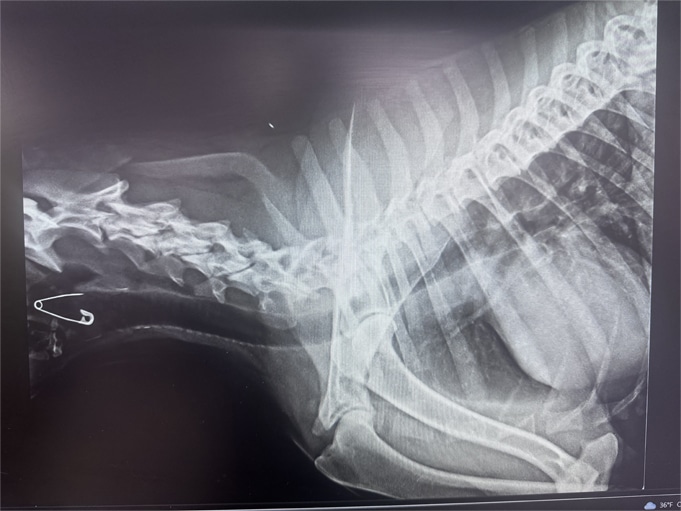

Can you see the foreign body in the pet's throat?

Digital X-Rays (Radiography)

Whether your pet is limping or having trouble breathing, radiographs (X-rays) give us a clear view of what’s happening internally. These high-resolution digital images help us detect:

With digital imaging, we can adjust image quality instantly, zoom in on problem areas, and share results with specialists if needed—all without waiting for film to develop.